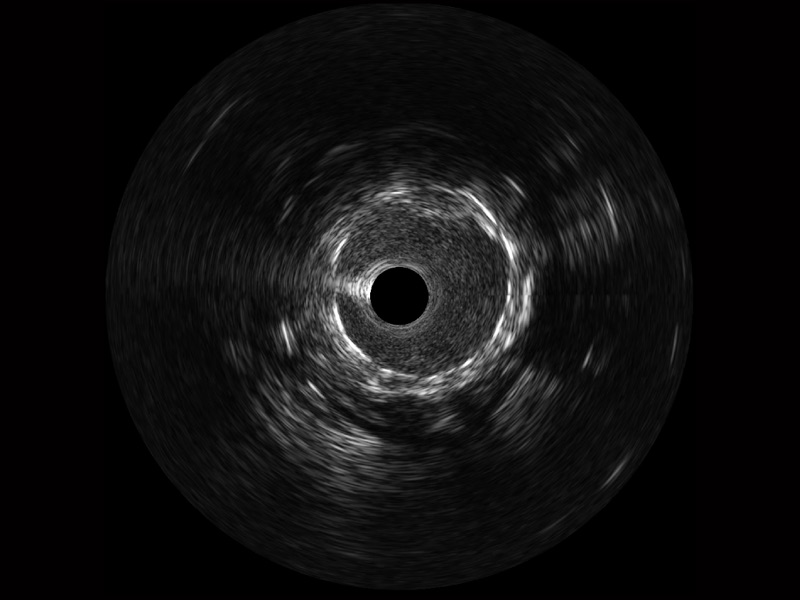

開立寬頻IVUS圖像

傳統(tǒng)IVUS圖像

對比傳統(tǒng)IVUS導(dǎo)管成像,開立寬頻IVUS圖像的近場支架梁顯影更細(xì)膩,遠(yuǎn)場中膜外血管仍清晰可辨,兼顧遠(yuǎn)中近,兼顧分辨力與穿透深度